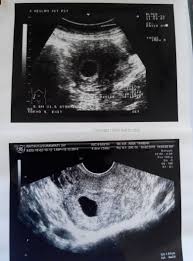

Penebalan dinding rahim membuat sulit hamil? Beberapa yang bisa menjadi indikator adalah: Haid lebih lama dengan volume darah yang juga lebih banyak. Karena pembesaran dan penebalan rahim itu tidak selalu menjadi ciri anda hamil ya. Hormon ini melenturkan leher rahim pada akhir kehamilan, sehingga bayi lebih mudah untuk keluar. Saat hasil test pack menunjukkan garis dua, yang segera dilakukan calon ibu baru adalah mengunjungi dokter sesegera mungkin. Sebenarnya, penebalan dinding rahim bukan suatu aktivitas dari kanker. Wanita yang sedang hamil muda biasanya mengalami kenaikan suhu tubuh sedikit di atas ambang normal, namun tidak sampai demam. Jika endometrium terlihat tebal, maka bisa saja hal ini menujukkan bahwa adanya penebalan dinding rahim, hiperplasia endometrium. Tanda tanda penebalan dinding adalah sebagai berikut. Simak penyebab dan gejala lainnya disini yuk! Cara menyembuhkan penebalan dinding rahim secara total cara menyembuhkan penebalan dinding rahim secara total paling ampuh terbukti sembuh total hanya dengan gamat emas kapsul yang sudah banyak terbukti menyembuhkan penebalan dinding rahim secara total dengan proses alami, aman dan tanpa efek samping selain itu juga sudah banyak kesaksian kesaksian konsumen kami yang sudah merasakan kesembuhan … Apakah siklus menstruasi ibu teratur atau tidak?.

Artinya, risiko kanker rahim atau operasi pengangkatan rahim bisa dihindari. Tindakan kuret juga bisa dilakukan untuk mendiagnosis suatu penyakit. Jika endometrium terlihat tebal, maka bisa saja hal ini menujukkan bahwa adanya penebalan dinding rahim, hiperplasia endometrium. Sekedar mengingatkan tanda hamil dan akan haid beda tipis jadi gak bisa dipastikan bunda hamil apa tidak, dan penebalan dinding rahim biasanya menandakan hamil atau akan haid. Menjaga ketebalan dinding rahim selama janin berkembang.